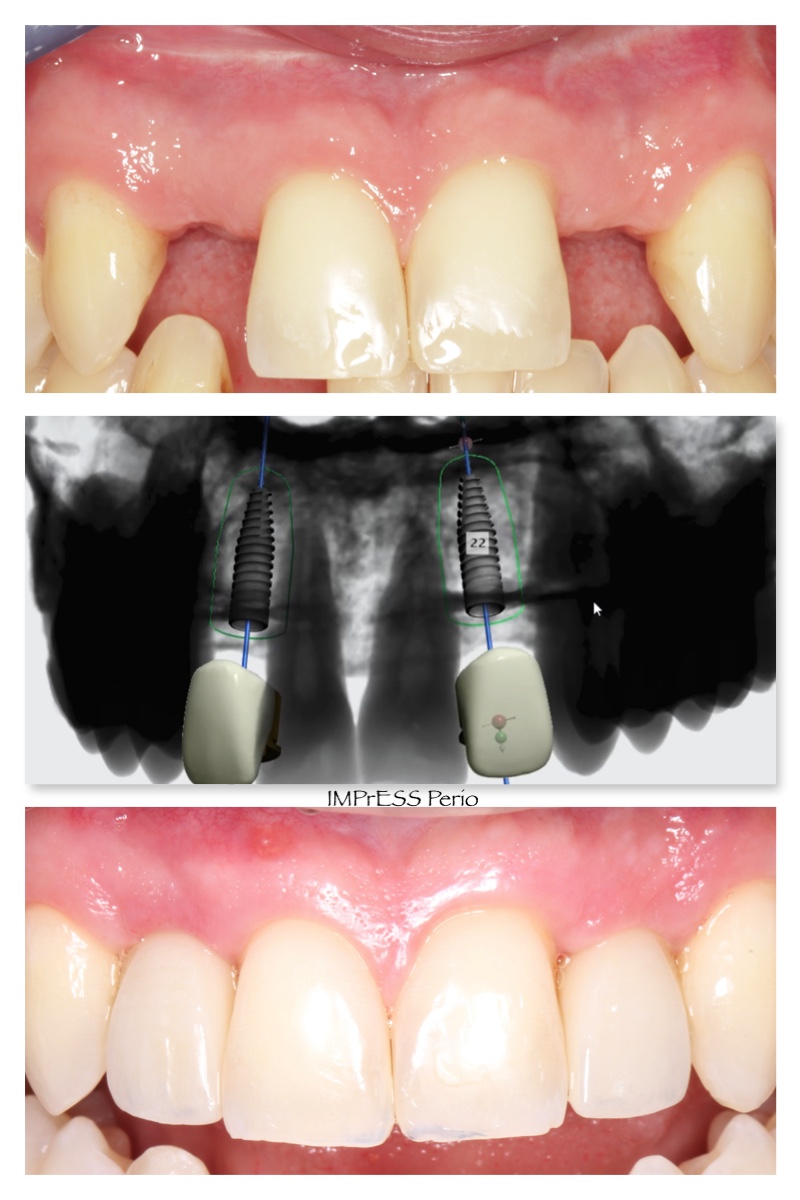

Before & Afters of Dental Implant Patients

Complete Dental Implant Cases Gallery

General Disclaimer: The results in the photographs are examples only and do not imply any certainty of the result of a procedure, and all outcomes are subject to the circumstances of the individual patient.